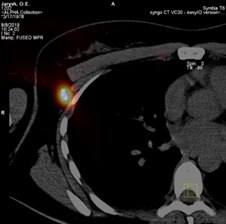

Пембролізумаб — один із ключових препаратів сучасної онкоімунології, який посилює здатність імунної системи виявляти та знищувати злоякісні клітини.

Препарат показує хороші результати при пізніх стадіях меланоми, коли хірургічне втручання вже неможливе, а імунотерапія стає єдиною ефективною стратегією боротьби з хворобою. Це не просто препарат — це надія, підкріплена наукою та практикою.